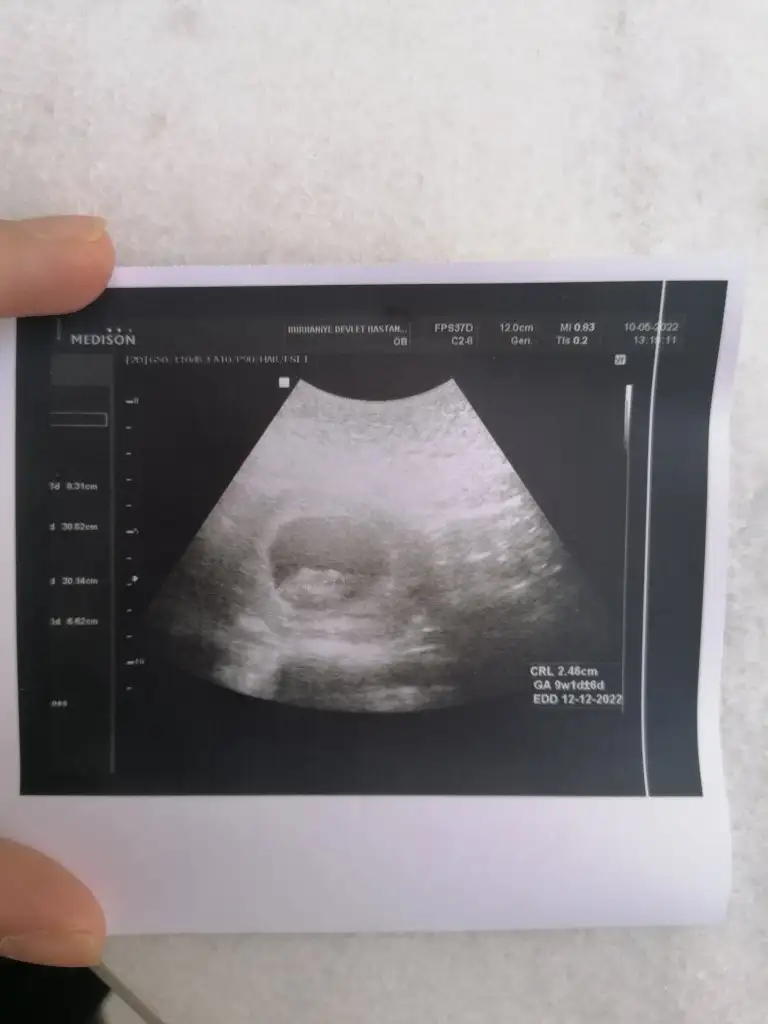

9+1 karından ultrason ile çekildi. Çok teşekkür ederim. Sevgiler.

paşa gibi 7 haftalık görüntüsü var mı?Merhaba Nur hanım rica etsem bana da bakar mısınız 9+0 karından